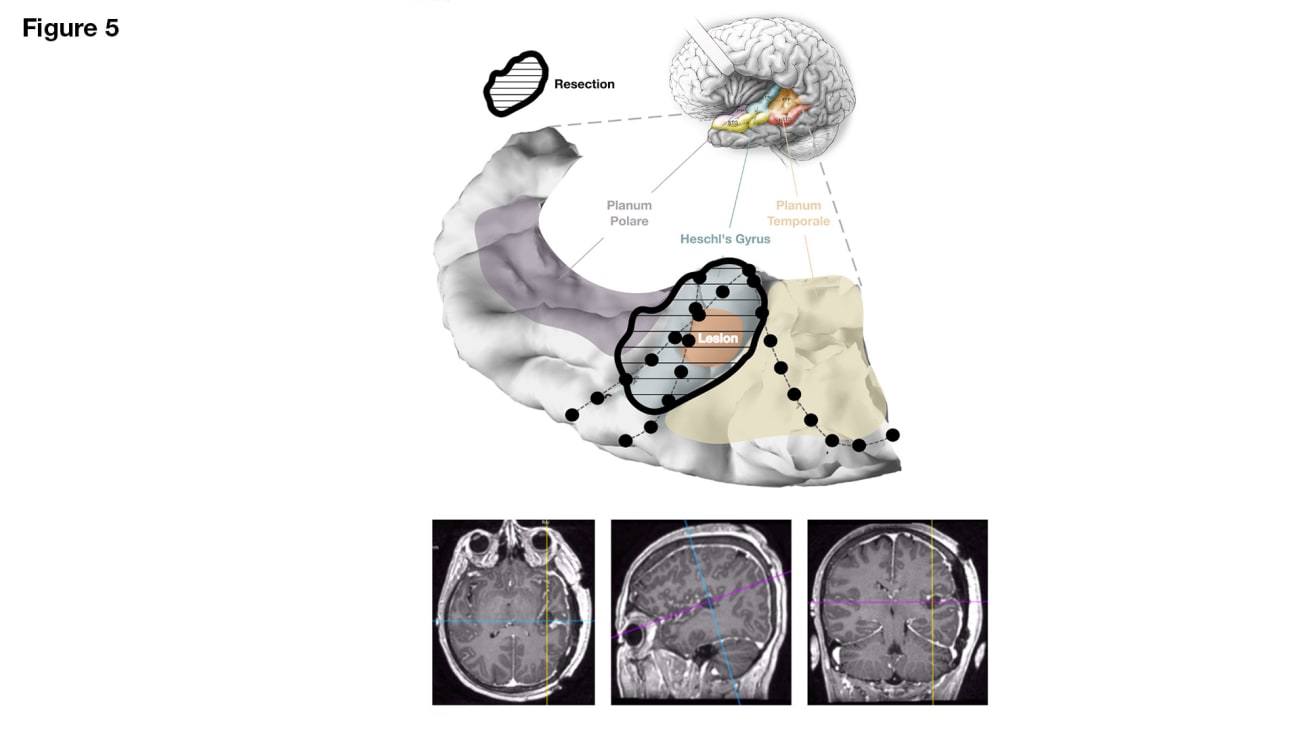

Given the reassuring speech mapping and new speech network models, the UCSF surgical team performed an electrocorticography-guided lesionectomy through a transsylvian approach (Video 1). Postoperative imaging showed complete resection of the lesion (Figure 5).

Postoperative MRI and reconstruction showing the resection margins with full removal of the lesion and Heschl’s gyrus.